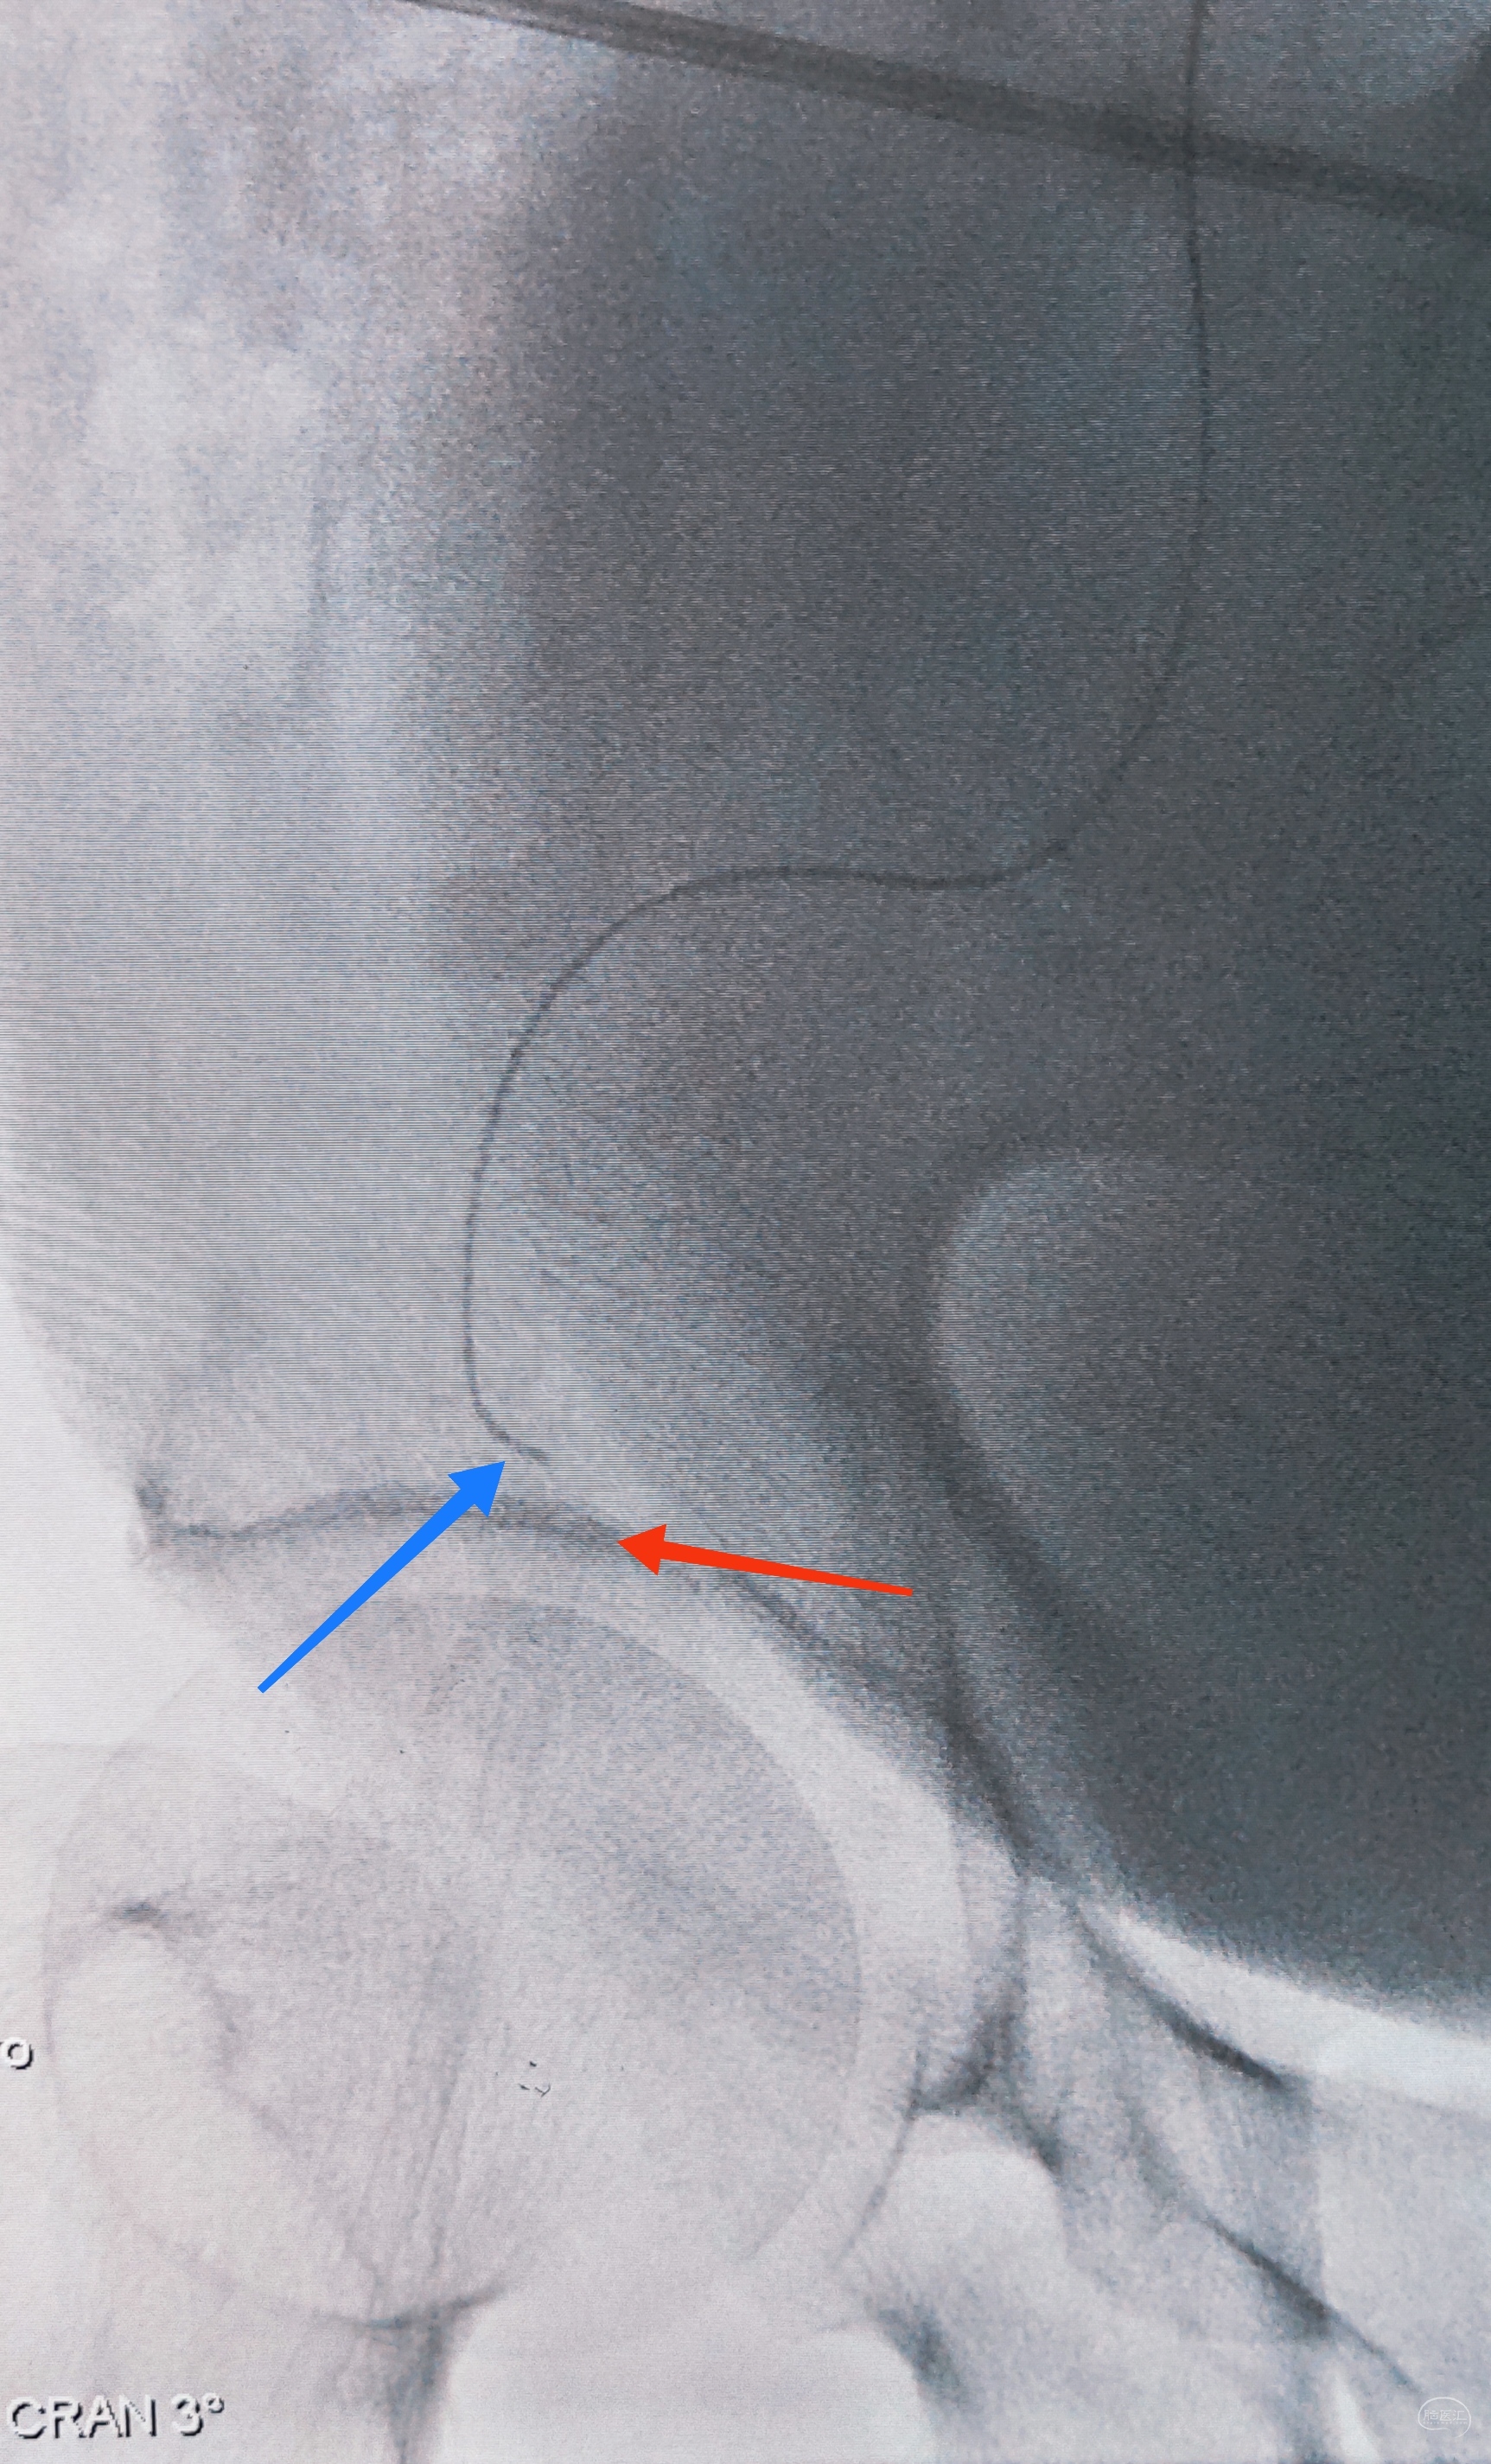

右侧颈总动脉正侧位造影:意料之外的是,枕动脉通过肌支与右侧椎动脉吻合(紫色箭头),像极了《大风吹》的歌词“借一杯天上的水”,源源不断进行着血流的补充。但是好景不长,同侧V4段明显狭窄,无情的设置了第二道坎(绿色箭头)。

左侧颈总动脉造影:颅内床突段以远基本闭塞,仅残涓涓细流,血供极差,脑膜中动脉瘤仅少量代偿,确实不容易,这估计就是想来搭桥的初衷了吧。